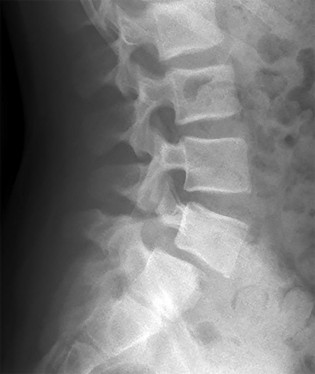

A 15-year-old female gymnast presents with persistent lower back pain. Lateral radiographs of the lumbar spine reveal a pars interarticularis defect at L5 and a forward translation of L5 on S1. The superior endplate of S1 is divided into four equal parts, and the posterior cortex of L5 sits over the second quartile. According to the Meyerding classification, what is the grade of this spondylolisthesis?